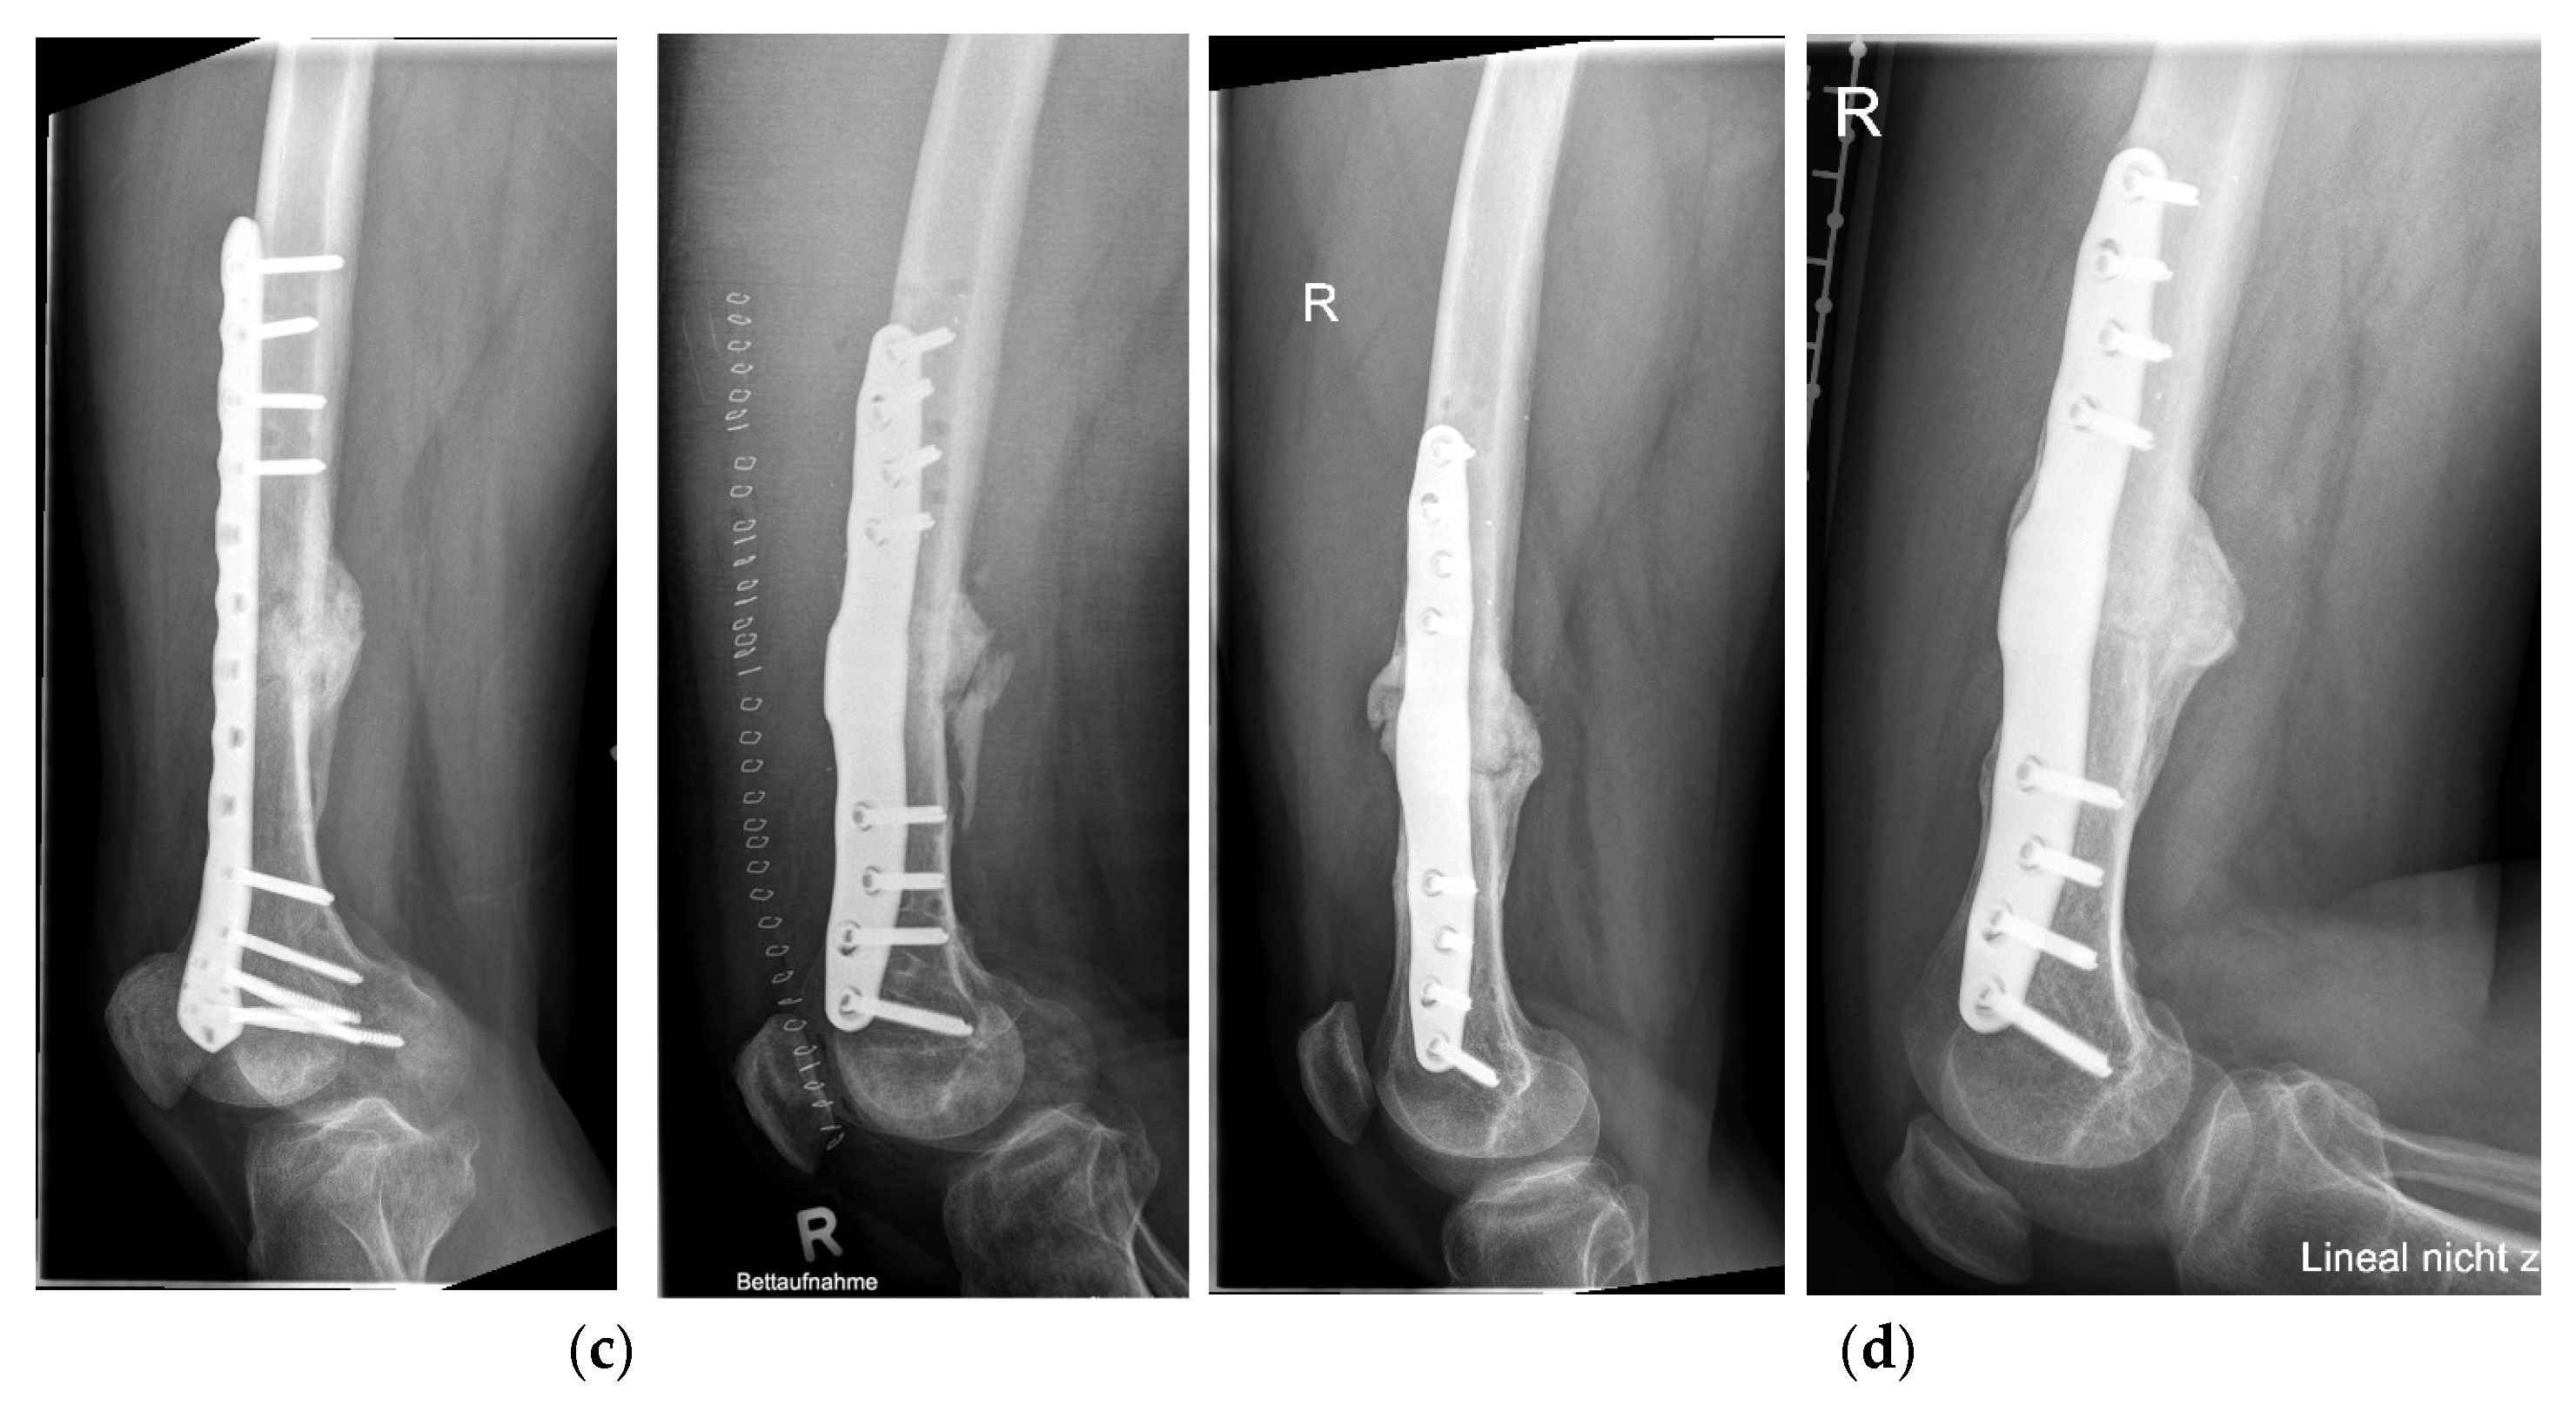

Postoperative Procedure and Further Course